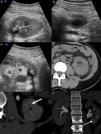

Renal colic is a common reason for presentation to emergency departments, and imaging has become fundamental for the diagnosis and clinical management of this condition. Ultrasonography and particularly noncontrast computed tomography have good diagnostic performance in diagnosing renal colic. Radiologic management will depend on the tools available at the center and on the characteristics of the patient. It is essential to use computed tomography techniques that minimize radiation and to use alternatives like ultrasonography in pregnant patients and children. In this article, we review the epidemiology, clinical and radiologic presentations, and clinical management of ureteral lithiasis.